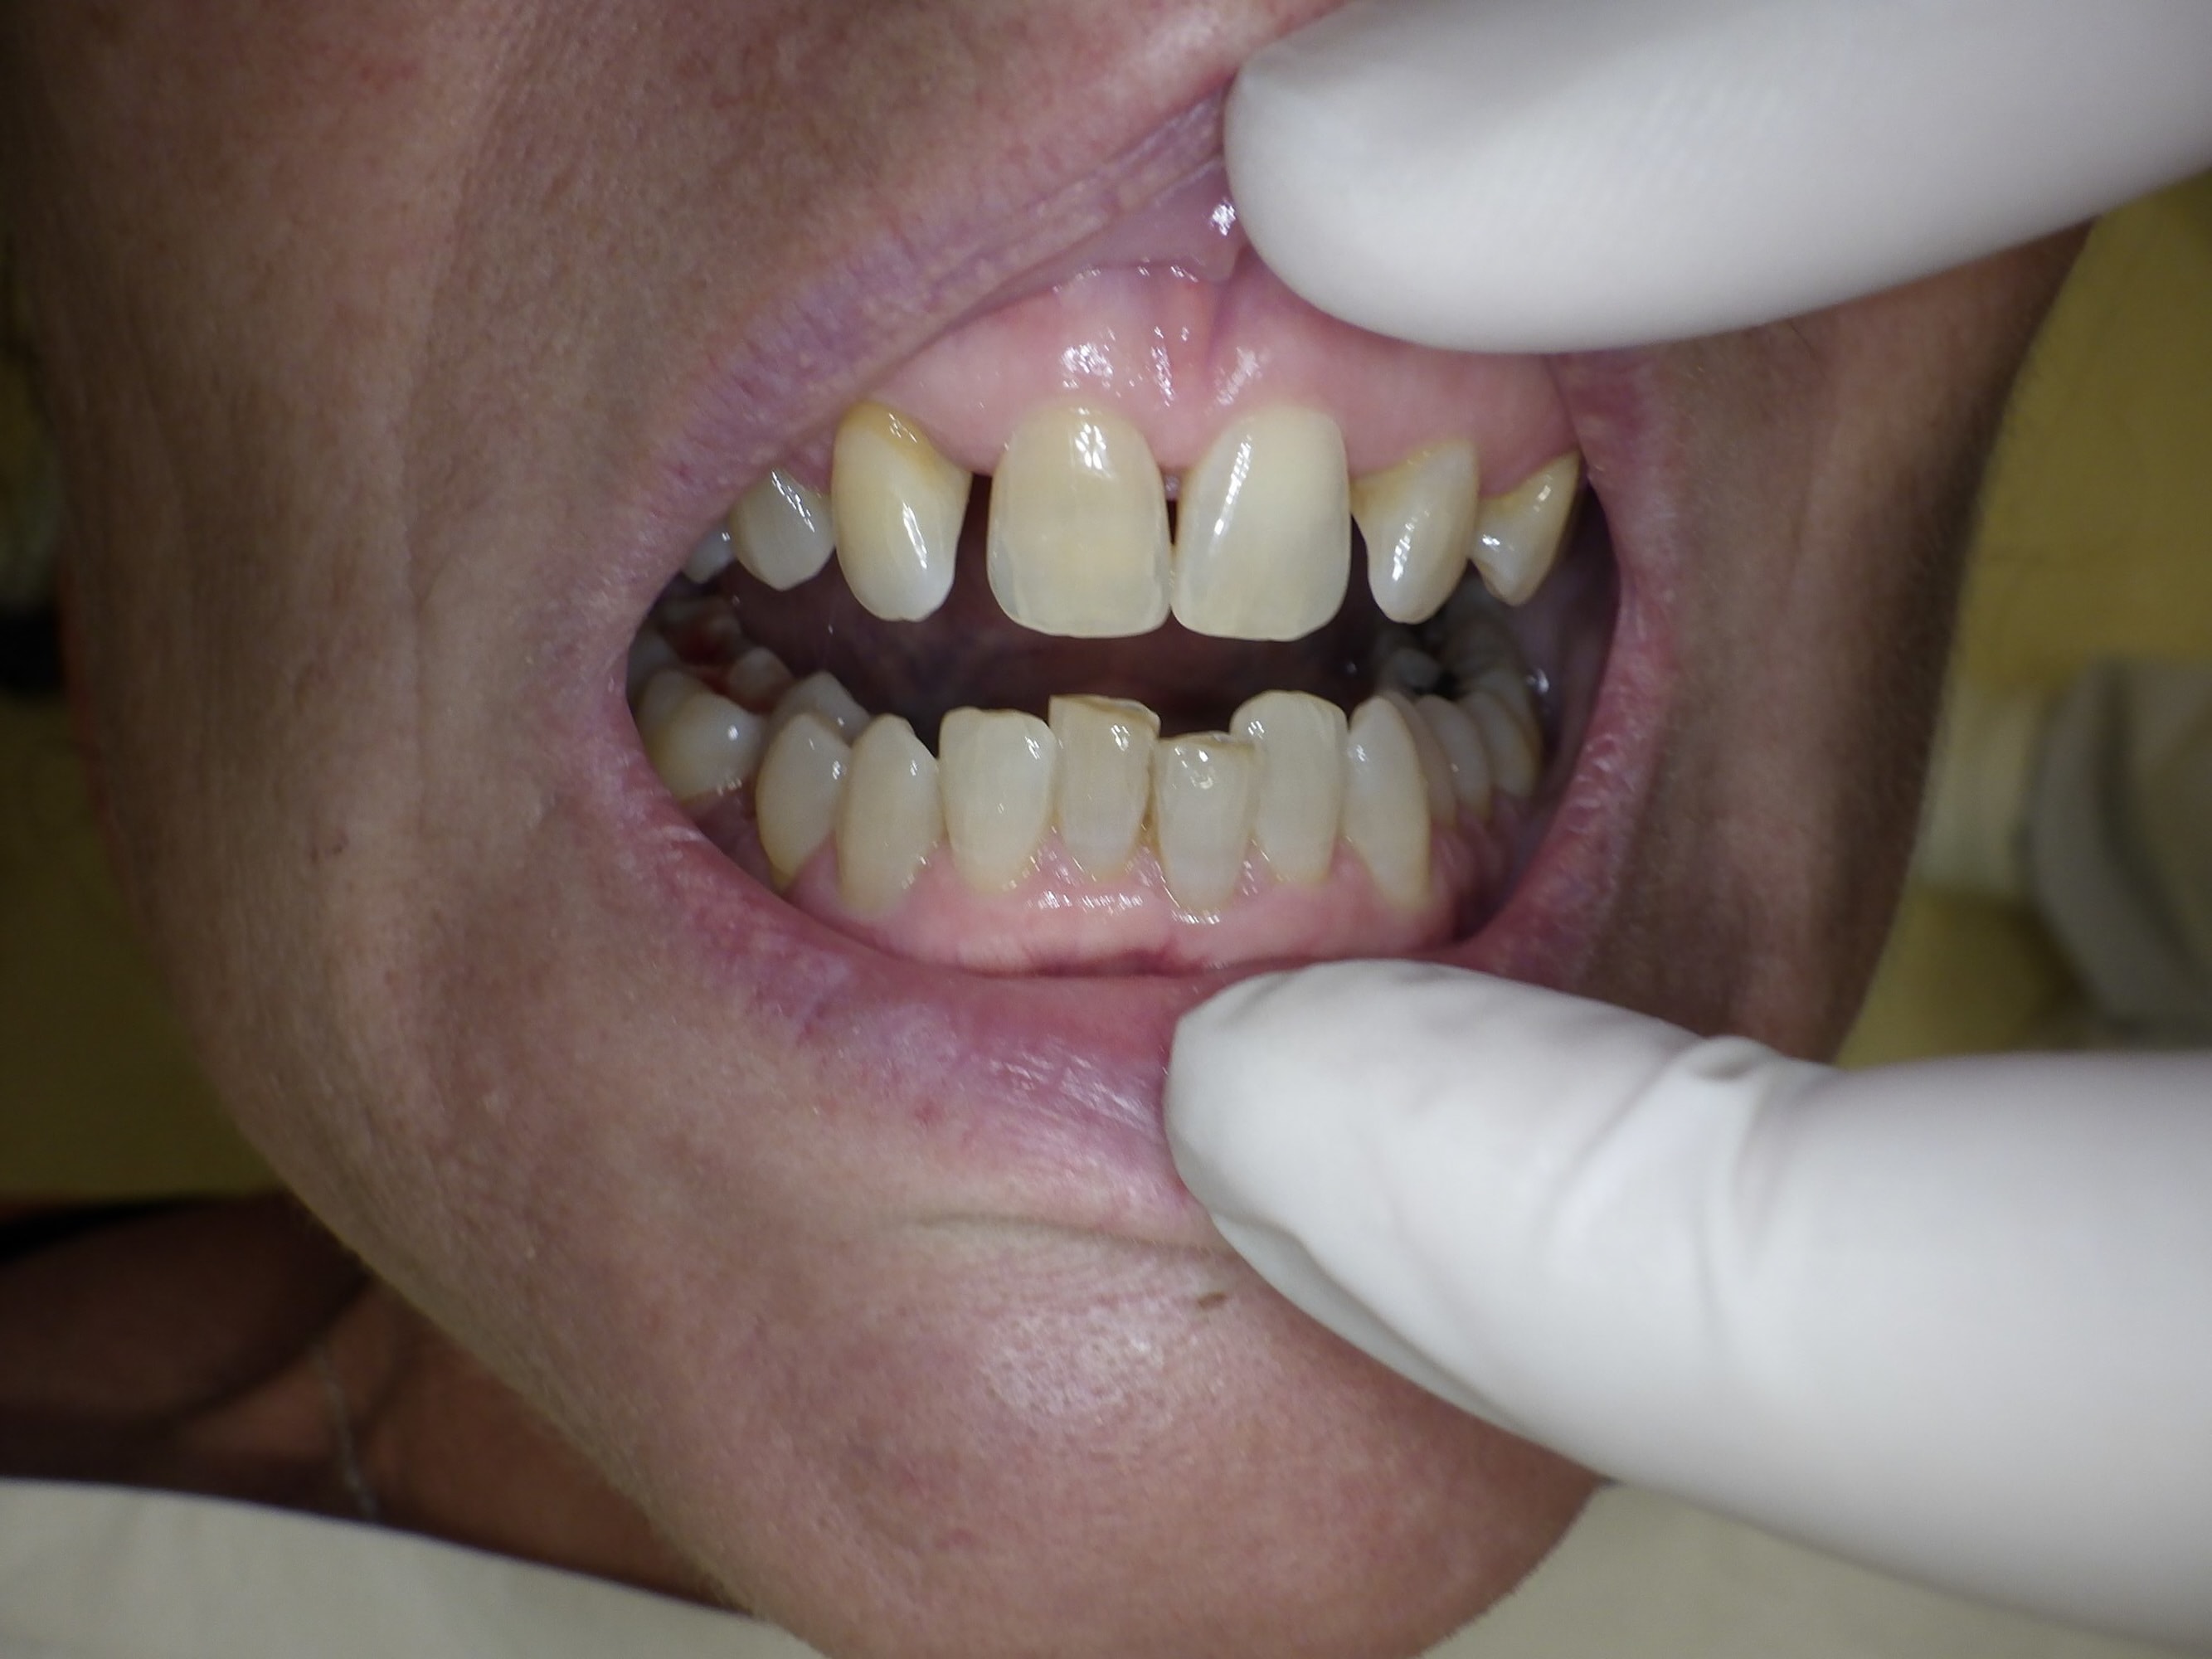

Bon afin de calmer le débat voici les photos de la patiente.

La 45 est en lingual et il y a eu de l'orthodontie suite à l'extraction de ses canines incluses lorsqu'elle avait 25 ans. (soit il y a 33 ans)

La 12 est en rotation mais ne bouge pas d'un poil.

Il y a un overbite énorme, donc pour l'équilibration, je ne vois pas trop comment faire.

J'y crois vachement plus maintenant comme facteur causal (ou en tout cas très fortement impliqué) avec un contact de l'antagoniste qui pousse systématiquement la 45 en lingual et entretient une desmodontite. Desmodontite qui à terme et sans doute cumulée avec une hygiène locale imparfaite (quasi impossible à maintenir vu la malposition) a finit par donner ce qu'on voit là.